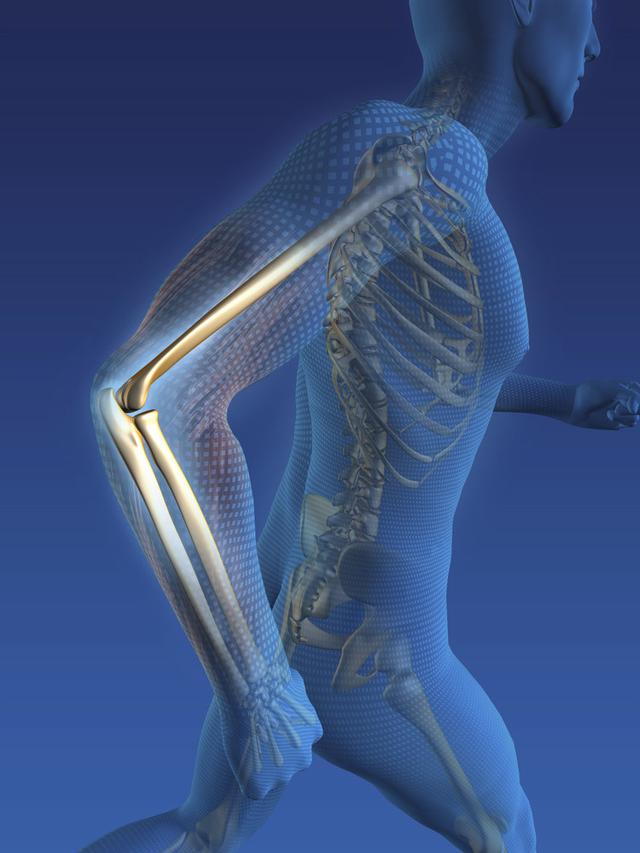

从一方面来说,人类是弱小的,容易生病,容易受伤,但从另一方面来说,人类也是强大的...